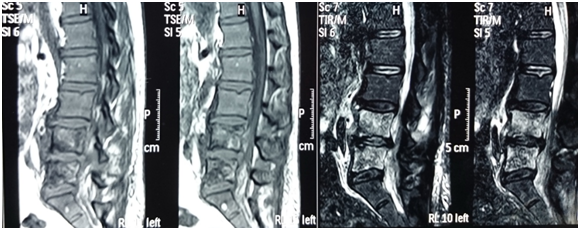

As patient still having backache, Magnetic Resonance Imaging (MRI) lumbo-sacral region was done to evaluate any deterioration in the disc prolapse state. Paraspinal mass was illustrated in MRI assessment (Figure 1) suggestive of metastatic lesion. So, bone scan was ordered to evaluate the nature of the lesion, and the results revealed neoplastic lesion involving L4 (Figure 2).

Figure 1 Non contrast MRI lumbosacral spine, bone marrow of L4 and L5 is seen replaced by abnormal SI in form of low SI on T1 and high SI on both T2 and STIR images?? Mostly metastatic lesion.

This what exactly happened to our case with normalization of liver function tests by proper treatment of her sepsis. Imaging studies including plain x-ray and CT could be useful. However, MRI is the most sensitive, radioisotope is a helpful adjunct, and biopsy (either percutaneous needle or open surgical) is generally needed to confirm the clinical and/or radiographic suspicion. Samples should be sent for aerobic, anaerobic, mycobacterial and fungal culture and pathology.

In our case, MRI suggested metastatic bone lesion which was changed to a diagnosis of paraspinal abscess on surgery indicating the mandatory need for confirmation of the diagnosis through biopsy. Surgical drainage of the paraspinal abscess under coverage of systemic antibiotic was the treatment of choice in this case as reported in literature.13